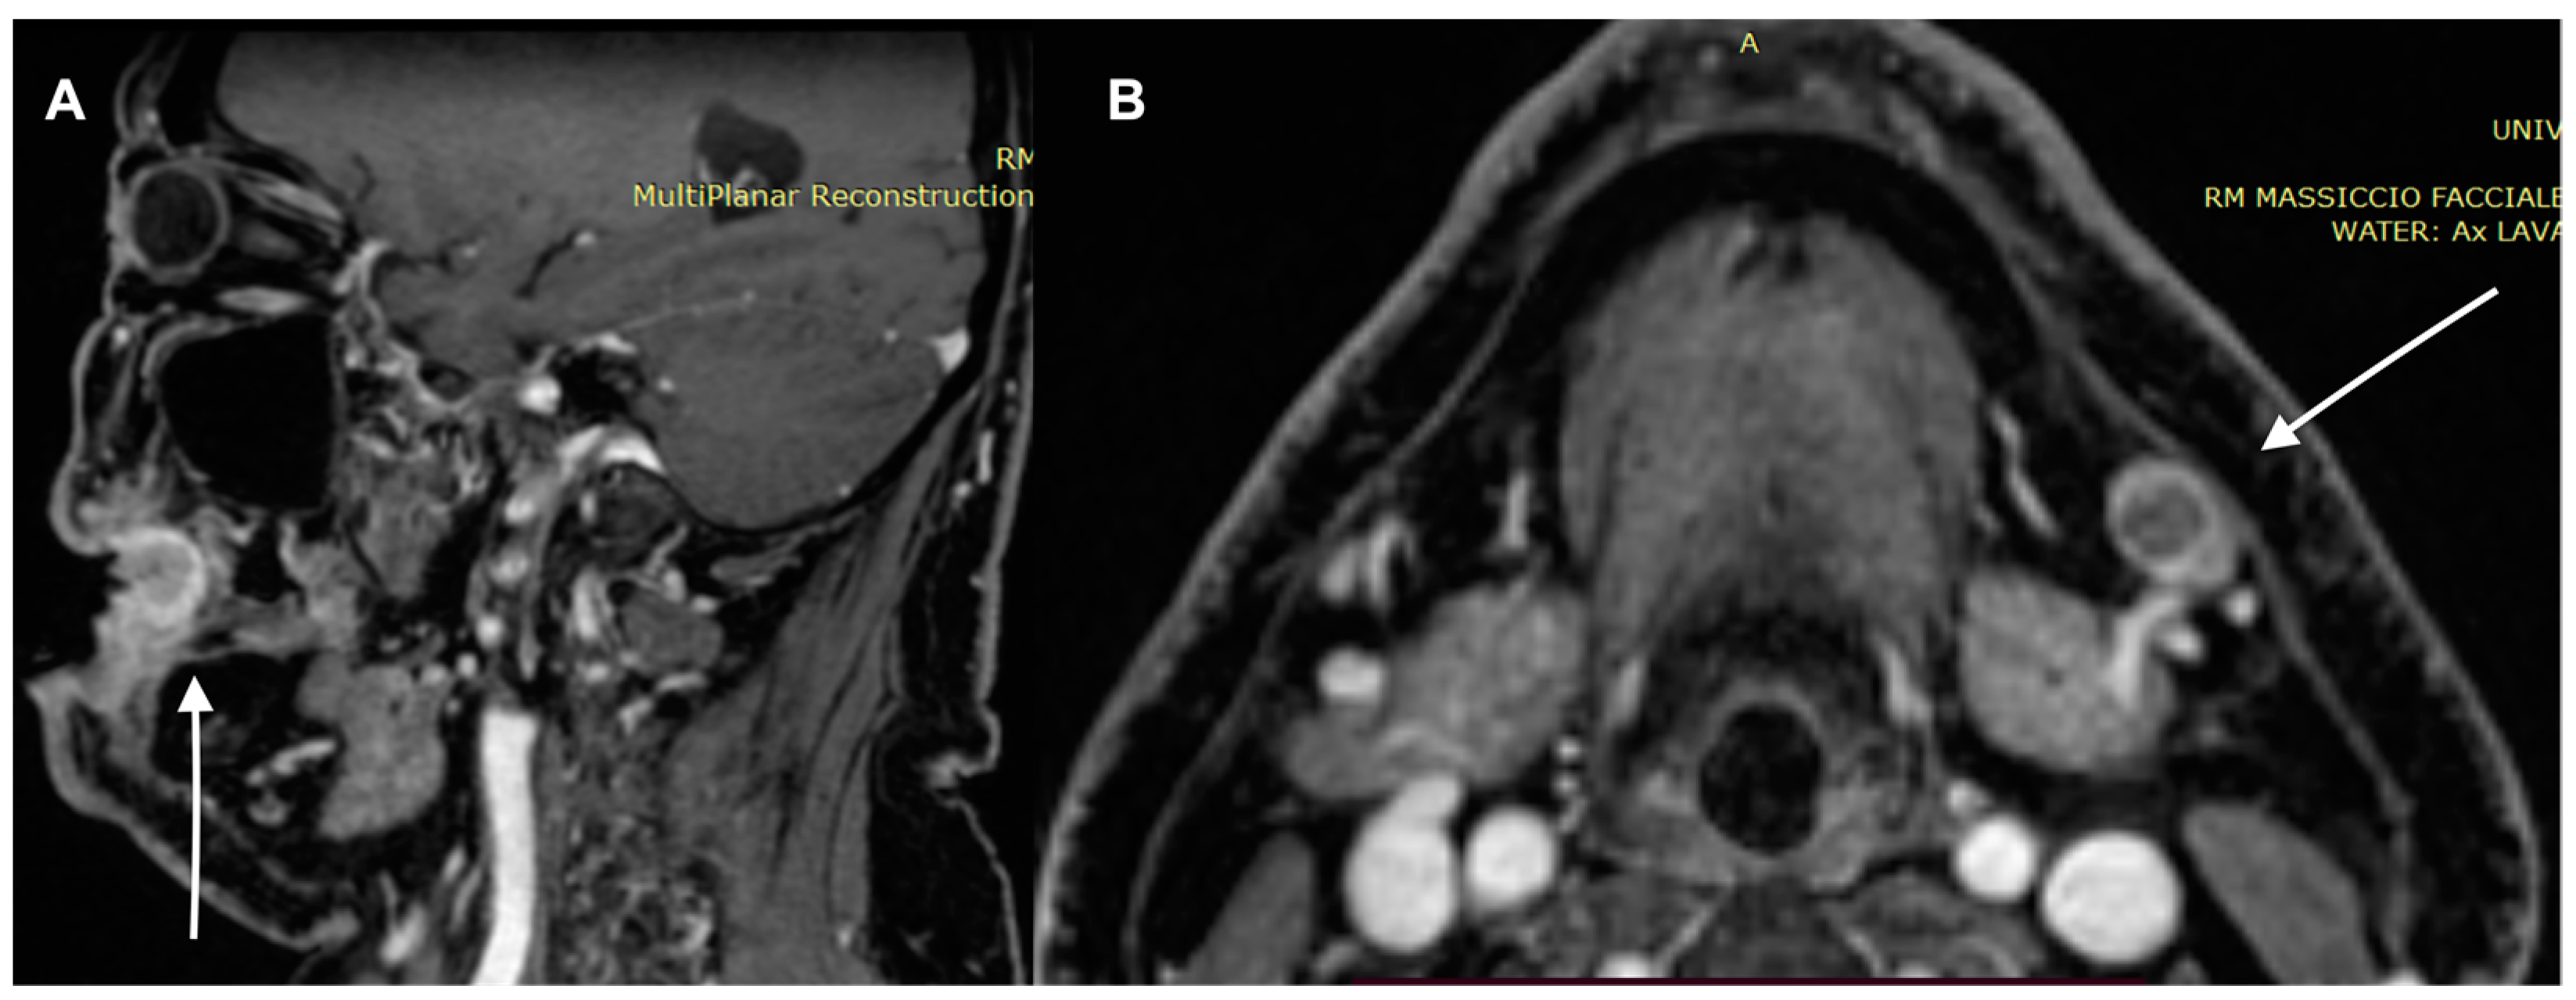

- Sheng, M.; Tang, M.; Lin, W.; Guo, L.; He, W.; Chen, W.; Li, K.; Liu, J.; Xiao, C.; Li, Y. The value of preoperative high-resolution MRI with microscopy coil for facial nonmelanoma skin cancers. Ski. Res. Technol. 2021, 27, 62–69. [Google Scholar] [CrossRef]

- Kawaguchi, M.; Kato, H.; Tomita, H.; Hara, A.; Suzui, N.; Miyazaki, T.; Matsuyama, K.; Seishima, M.; Matsuo, M. Magnetic Resonance Imaging Findings Differentiating Cutaneous Basal Cell Carcinoma from Squamous Cell Carcinoma in the Head and Neck Region. Korean J. Radiol. 2020, 21, 325–331. [Google Scholar] [CrossRef] [PubMed]